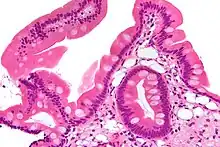

Low magnification micrograph of Whipple's disease showing the characteristic foamy appearing infiltrate of the lamina propria. Duodenal biopsy. H&E stain.

Endoscopy of the duodenum and jejunum can reveal pale yellow shaggy mucosa with erythematous eroded patches in patients with classic intestinal Whipple's disease, and small bowel X-rays may show some thickened folds. Other pathological findings may include enlarged mesenteric lymph nodes, hypercellularity of lamina propria with "foamy macrophages", and a concurrent decreased number of lymphocytes and plasma cells, per high power field view of the biopsy.